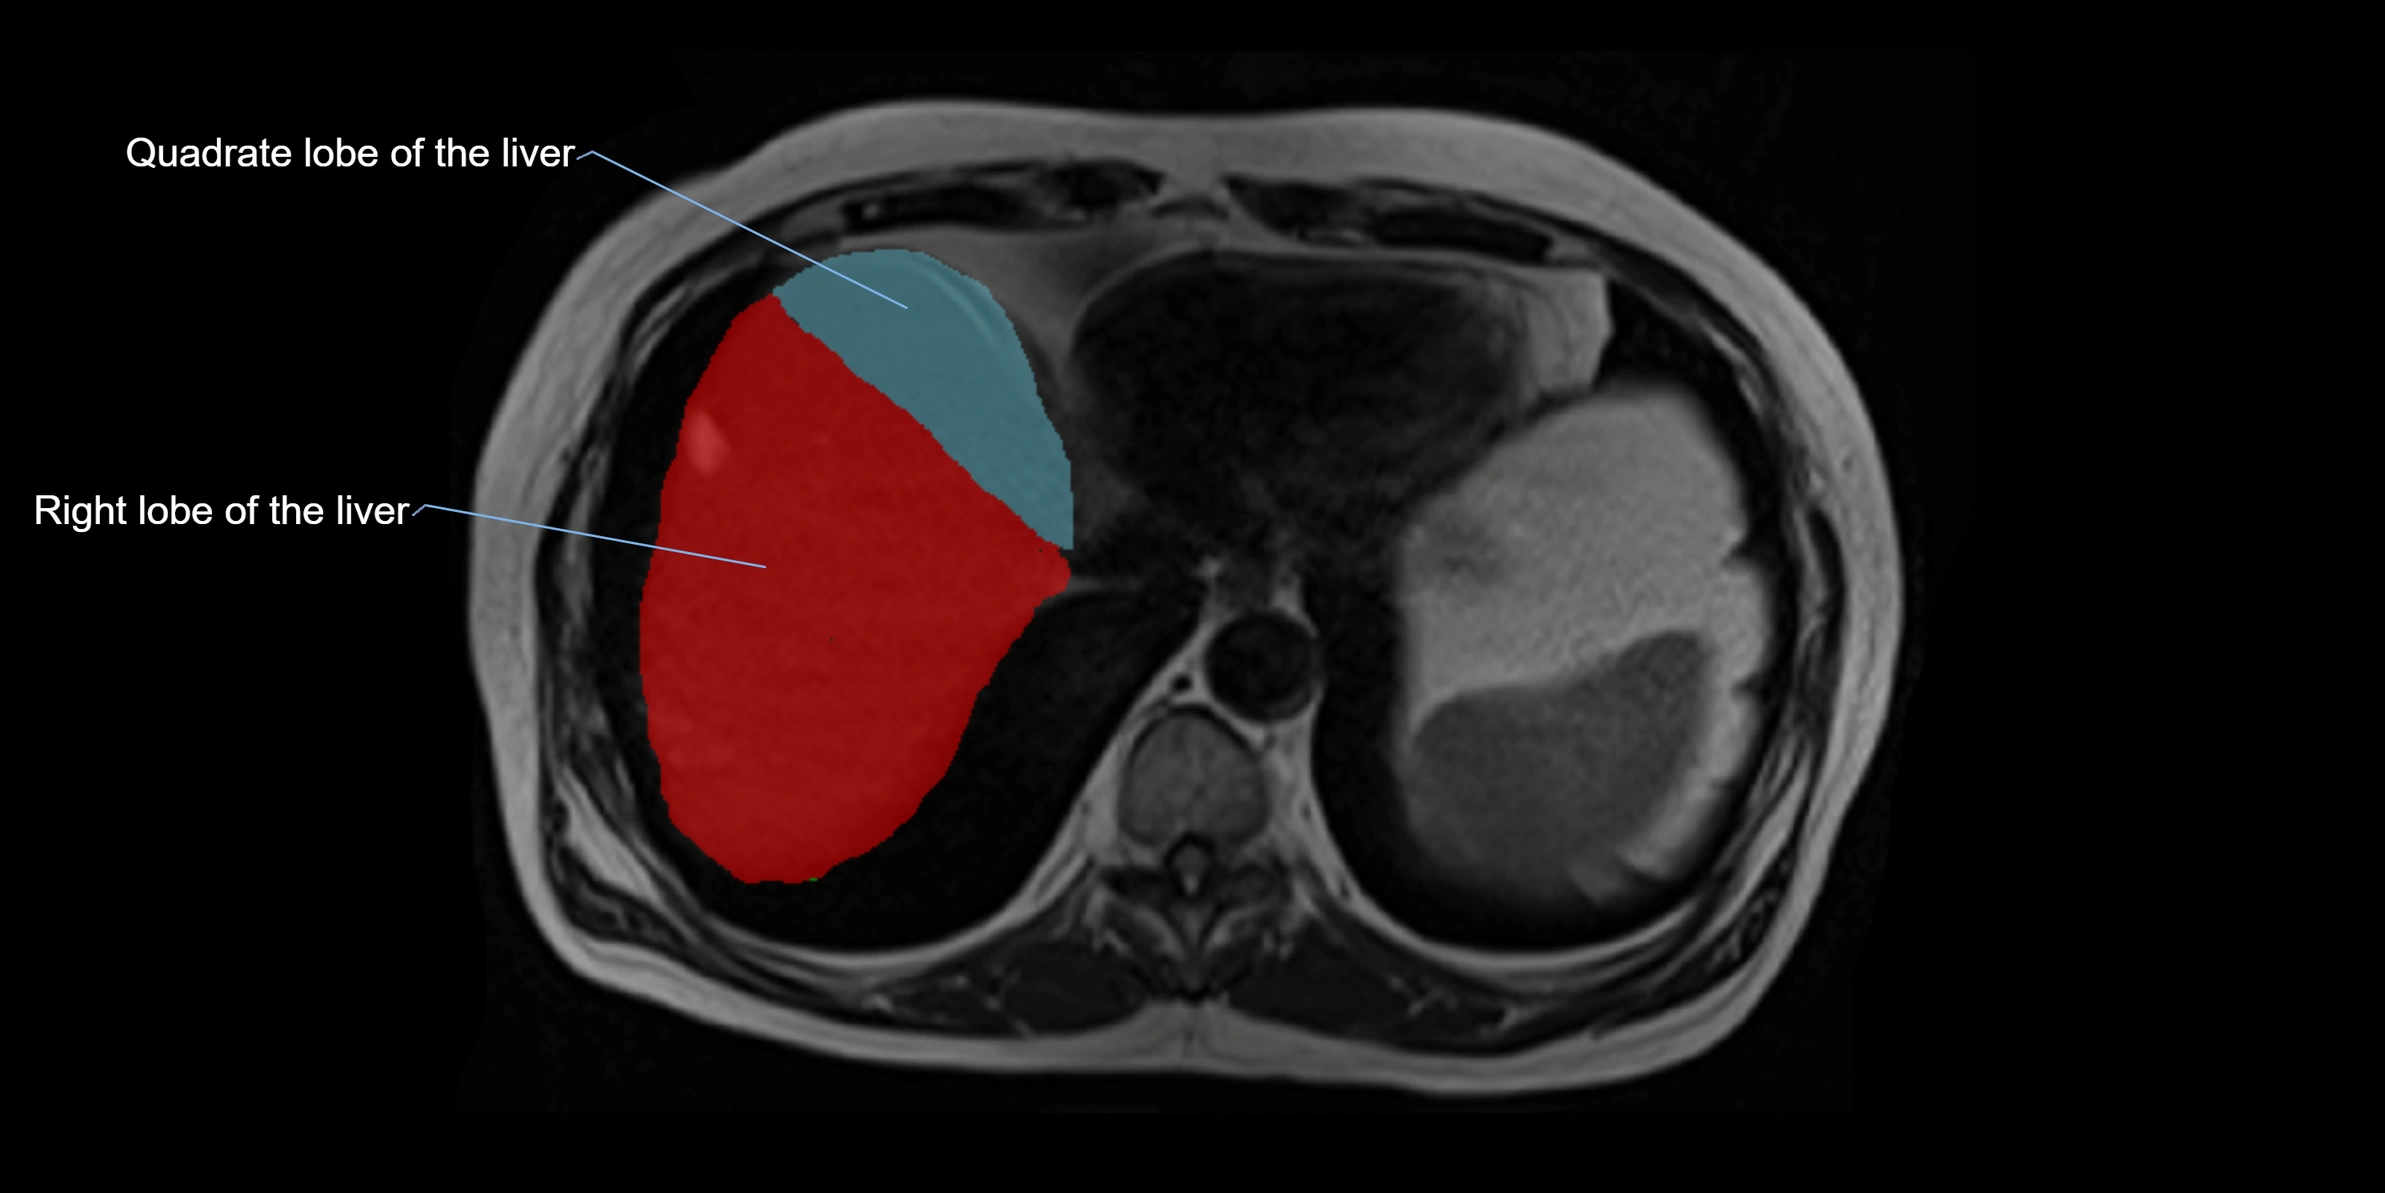

The caudate lobe of the liver is a distinct anatomical subdivision of the liver, designated as segment I in Couinaud’s classification. It lies on the posterior surface of the liver, between the fissure for the ligamentum venosum (left boundary) and the groove for the inferior vena cava (IVC) (right boundary). Superiorly, it is related to the posterior liver surface, and inferiorly it is separated from the left lobe by the porta hepatis.

MRI Appearance

T1-weighted images:

• Parenchyma shows intermediate signal intensity, similar to rest of liver

• Lesions (tumors, fat, fibrosis) show altered signal compared to background liver

T2-weighted images:

• Normal parenchyma shows intermediate to slightly hyperintense signal

• Pathologies (cysts, hemangiomas, tumors) demonstrate variable high signal